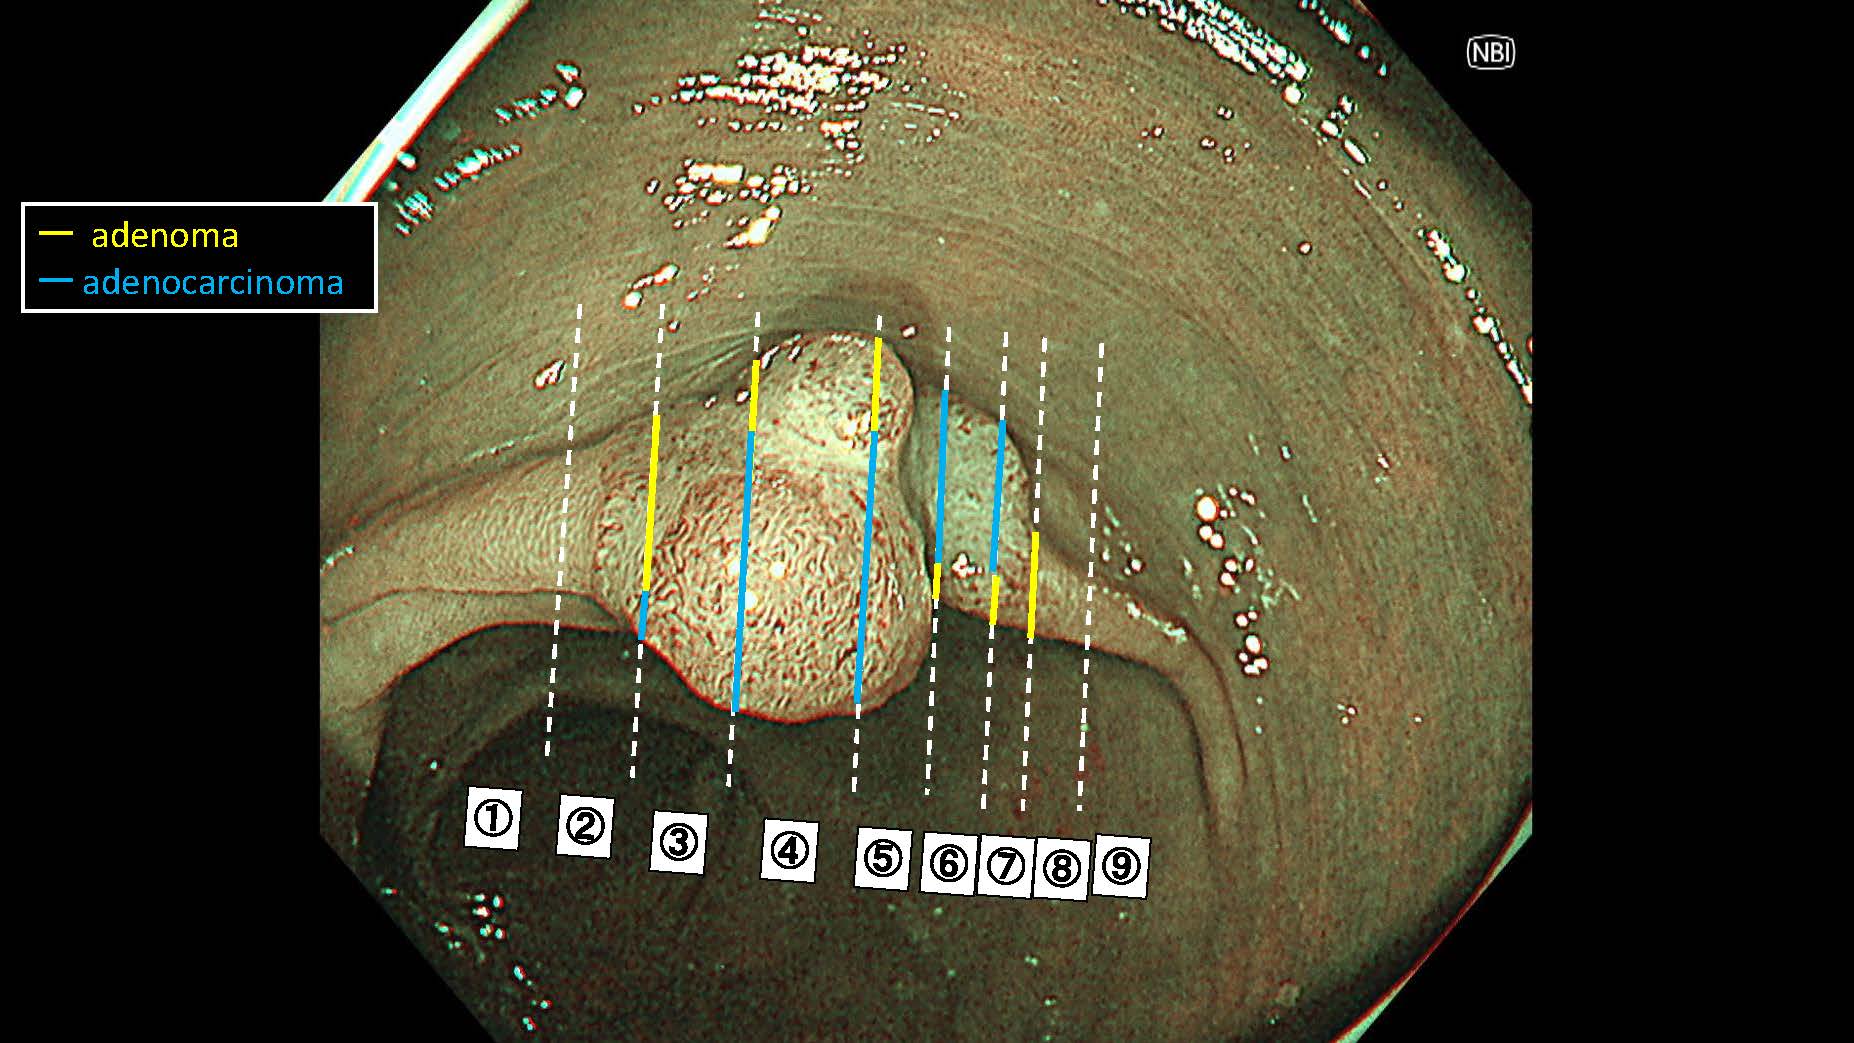

消化管Mapping~大腸~ 2025.6.11

消化管Mapping

消化管Mapping~大腸~

消化器内科

内視鏡検査・治療